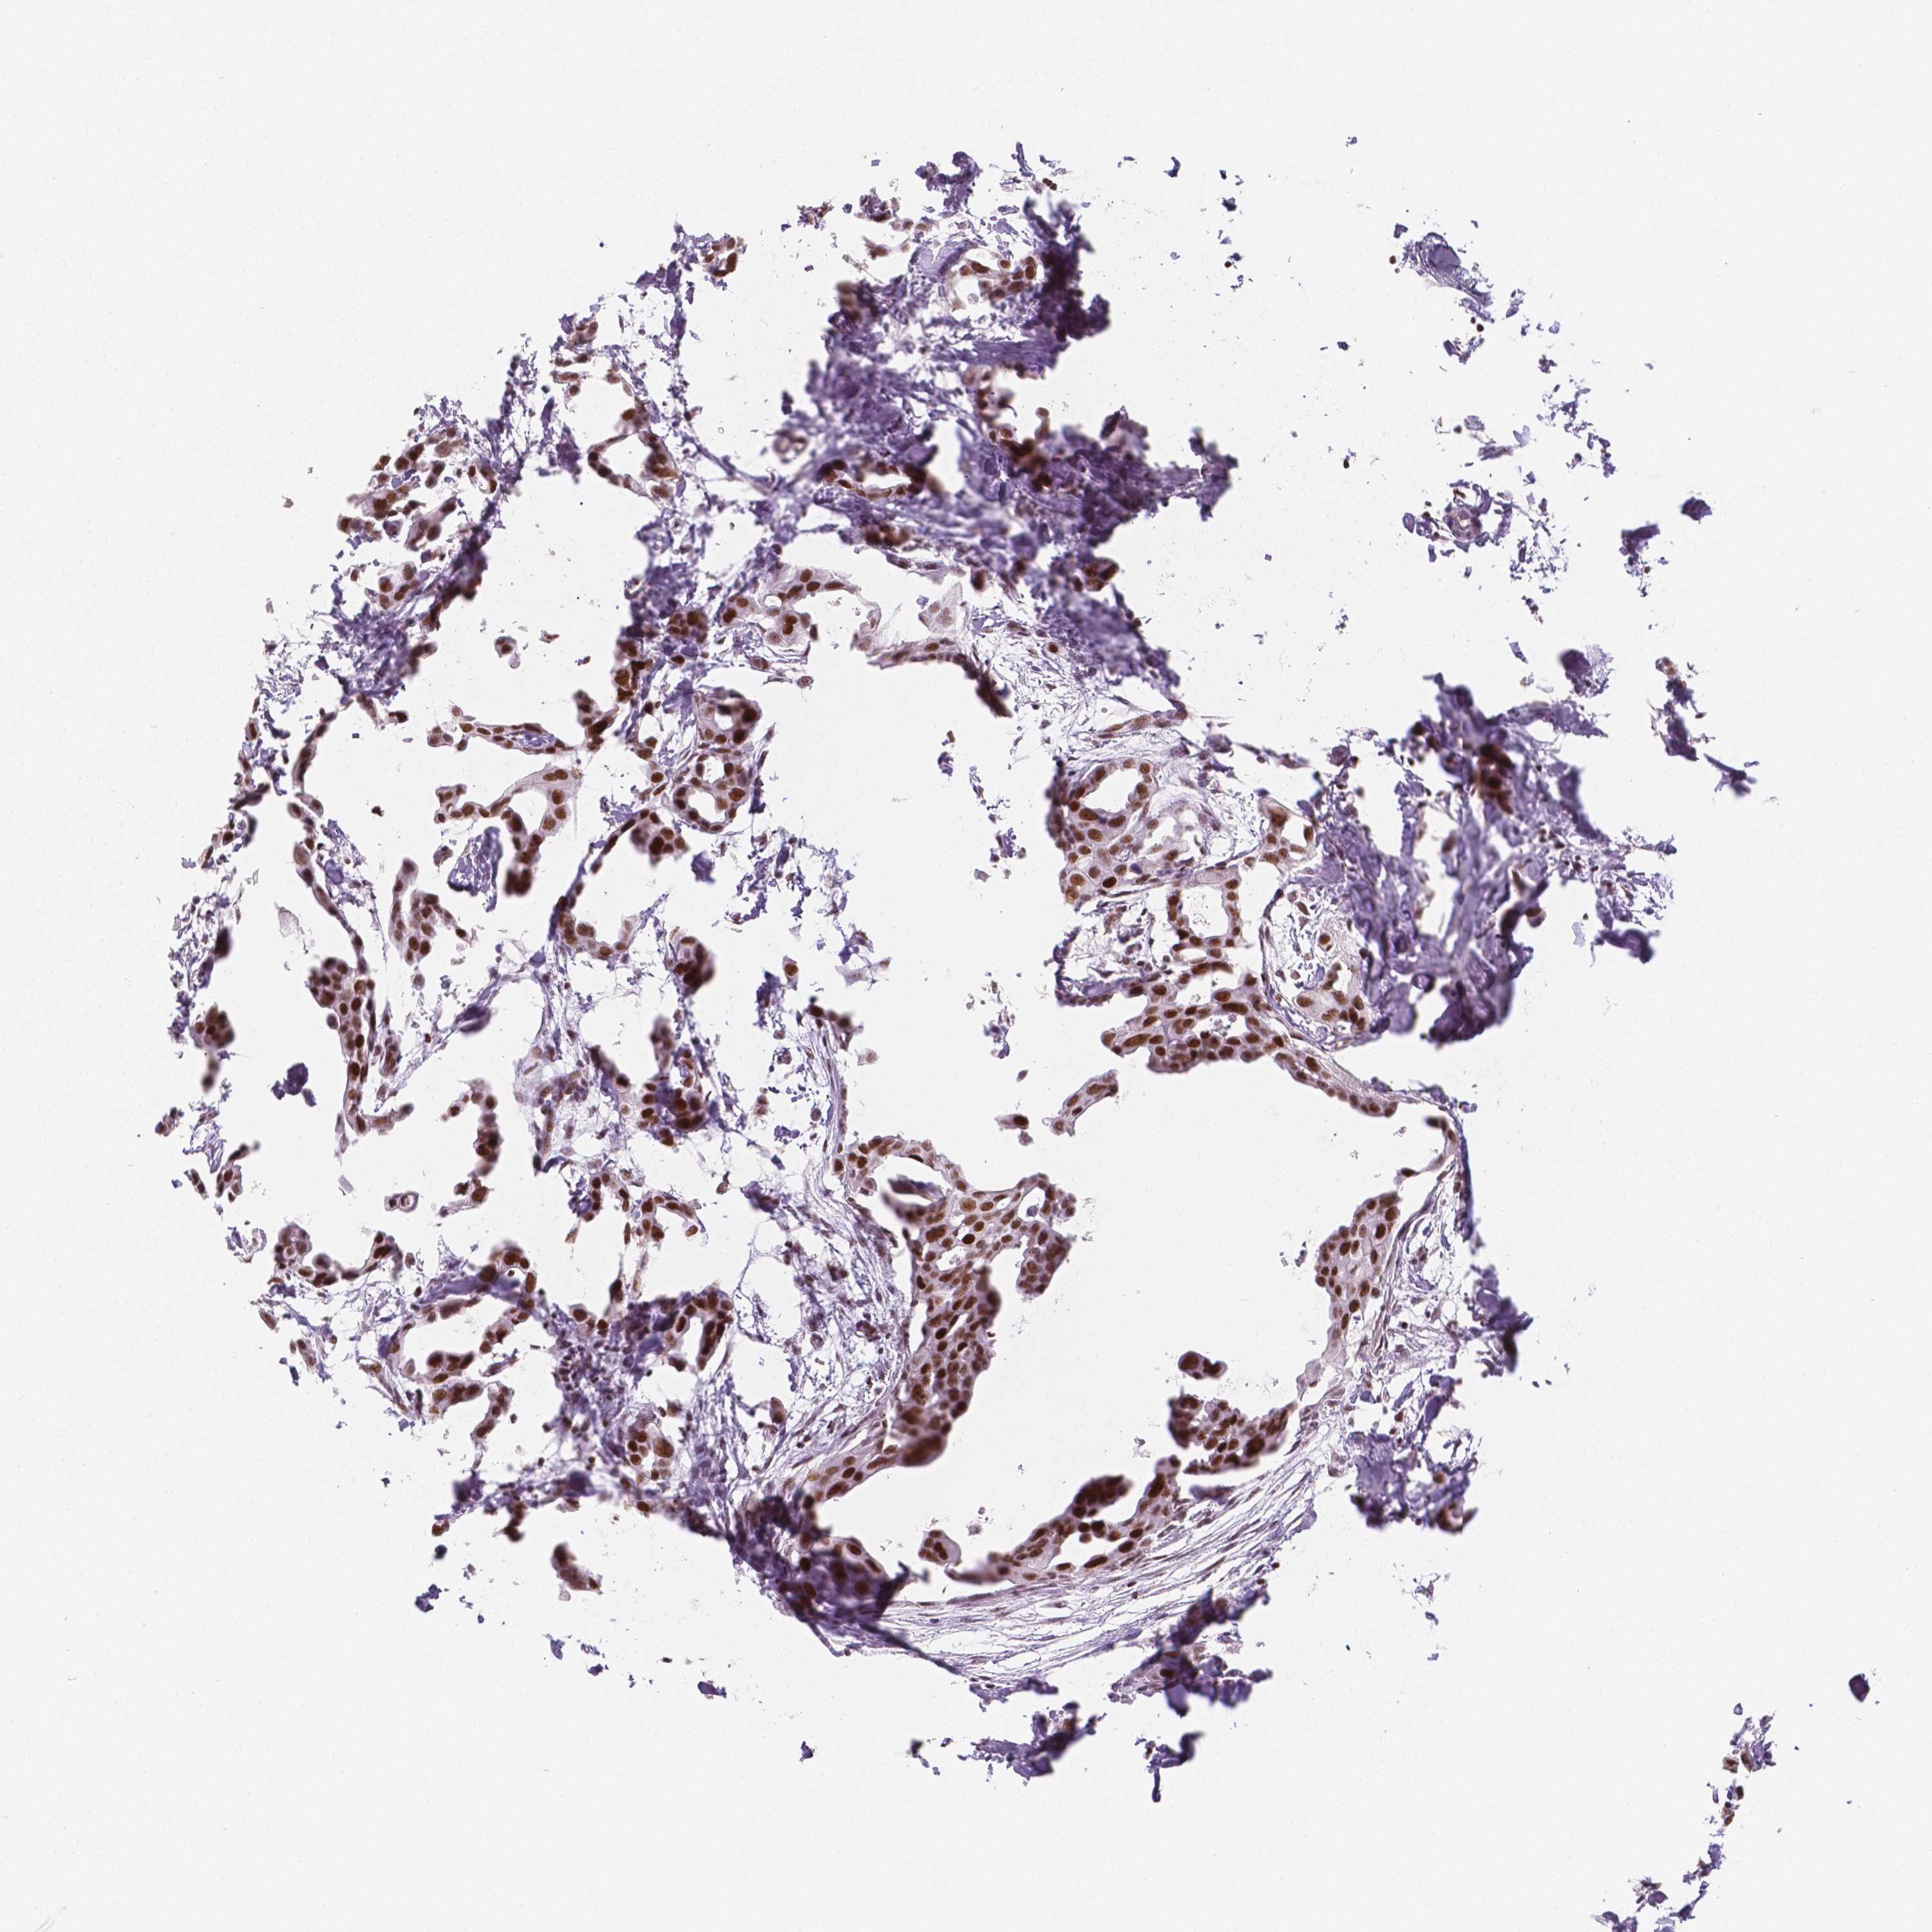

BRCA TCGA BRCA VALIDATION PROTEIN EXPRESSION

ANTIBODIES

AND

VALIDATION